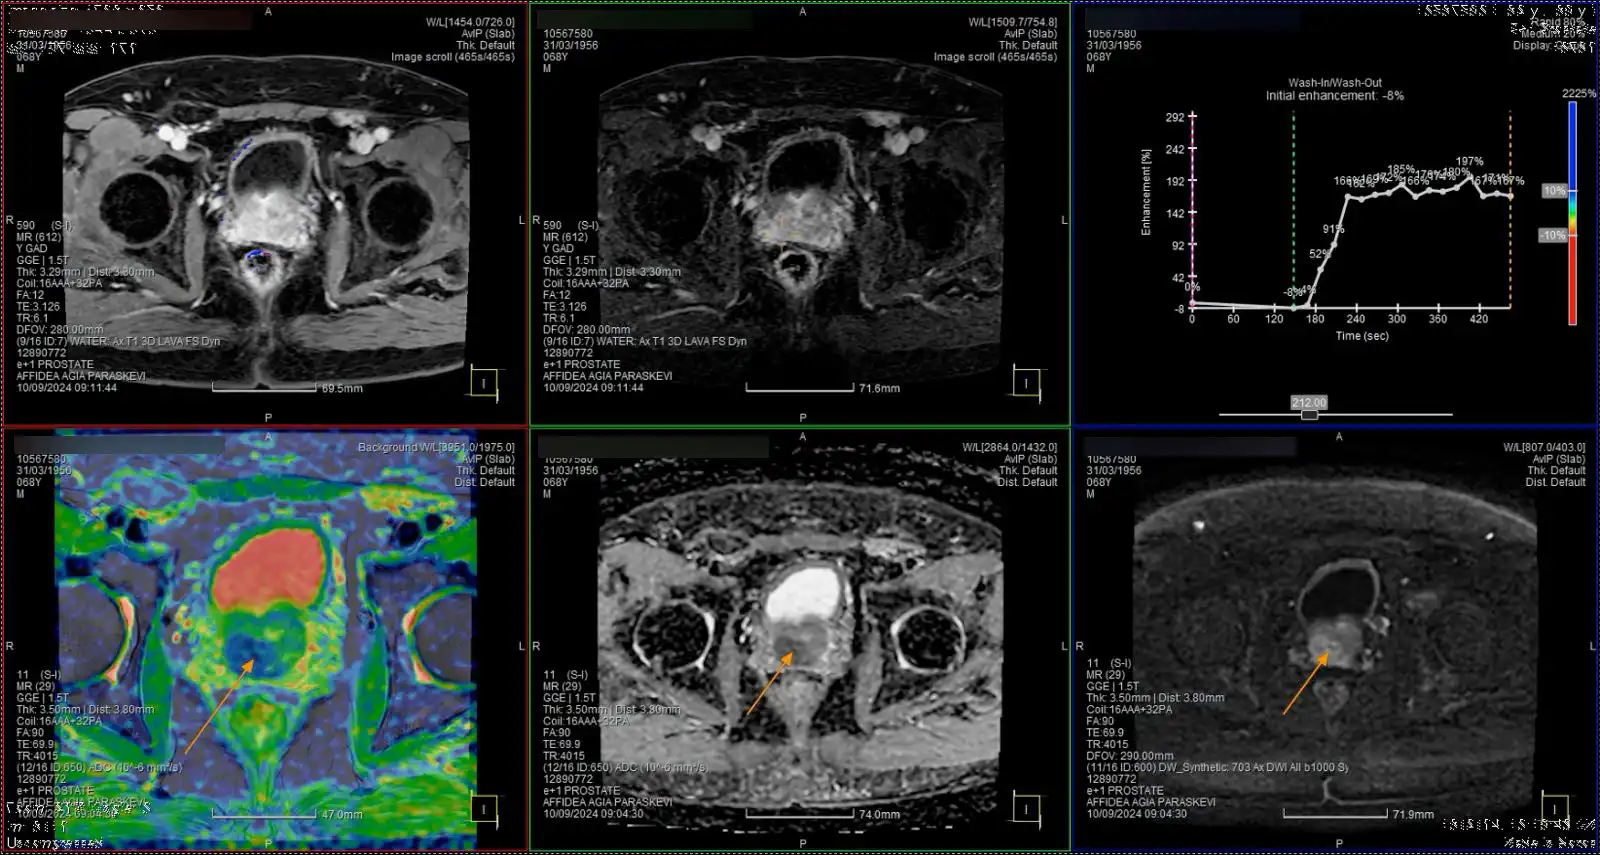

Η χρήση της πολυπαραμετρικής MRI στην διάγνωση του Καρκίνου του Προστάτη

Το 2018 ήταν η χρονιά που σε αρκετά έγκριτα περιοδικά (New England Journal of Medicine, European Urology, Lancet Oncology) δημοσιεύτηκαν μελέτες πάνω στο θέμα του καρκίνου του προστάτη. Οι μελέτες αυτές απέδειξαν την χρησιμότητα της πολυπαραμετρικής ΜRI στην αρχική διάγνωση. Κοινό συμπέρασμα σε όλες τις μελέτες ήταν η χρήση της πολυπαραμετρικής μαγνητικής τομογραφίας. Αυτό οδήγησε στην διάγνωση περισσότερων κλινικά σημαντικά καρκίνων.

Ποσοστά 38,32,25% στις μελέτες PRECISION, MRI first, 4M για το θέμα του καρκίνου του προστάτη αντίστοιχα, συγκρινόμενες με την κλασσική βιοψία με την χρήση διορθικού υπερήχου ποσοστά 26,30,32% αντίστοιχα. Παράλληλα ανίχνευσε κλινικά μη σημαντικούς καρκίνους σε ποσοστά 9,6&14%. Τα ποσοστά αυτά είναι σημαντικά χαμηλότερα από την συμβατική βιοψία (22,20,25%). Επιπλέον σε ποσοστό που κυμάνθηκε από 14-49% οι ασθενείς δεν χρειάστηκε να υποβληθούν σε βιοψία.

Τα μειονεκτήματα της νέας αυτής μεθόδου είναι ότι το αποτέλεσμα μπορεί να επηρεαστεί. Ένας παράγοντας είναι η εμπειρία του ακτινοδιαγνώστη και την ακρίβεια του μηχανήματος που θα θέσει την διάγνωση. Αυτό αποτέλεσε και ένα από τα σημεία σχολιασμού στις μελέτες. Οι περισσότεροι ασθενείς διαγνώστηκαν σε συγκεκριμένα κέντρα με μεγάλη εμπειρία . Ένα ακόμα μειονέκτημα αποτελεί το υψηλό της κόστος ακόμα και σε ανεπτυγμένες οικονομικά χώρες , μπορεί να αναλογιστεί κανείς το κόστος πχ για 250.000 ασθενείς στην Γαλλία που κάνουν βιοψία τον χρόνο.